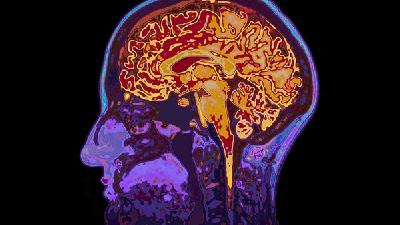

如何预防婴儿脑瘫

预防婴儿脑瘫需从孕期保健、分娩管理、新生儿护理等多方面入手,主要包括规范产检、避免早产、预防感染、减少脑损伤风险等措施。